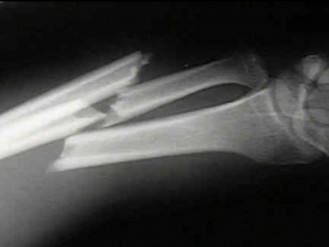

ആശുപത്രിയില് ചികിത്സയിലിരിക്കെ രോഗി നഴ്സിന്റെ കൈ തല്ലിയൊടിച്ചു. കൊല്ലം ജില്ലയിലെ കടയ്ക്കല് താലൂക്ക് ആശുപത്രിയില അസിസ്റ്റന്റ് നഴ്സ് വിമലയാണ് ആക്രമണത്തിനിരയായത്. ആശുപത്രിയില് ചികിത്സയിലായിരുന്ന ശ്രീകുമാര് എന്ന രോഗിയാണ് നഴ്സിനെ ആക്രമിച്ചത്. ഇയാള് ആക്രമിക്കാനുണ്ടായ കാരണം വ്യക്തമല്ല. ചികിത്സയിലായിരുന്ന ശ്രീകുമാറിനെ പോലീസ് അറസ്റ്റു ചെയ്തു